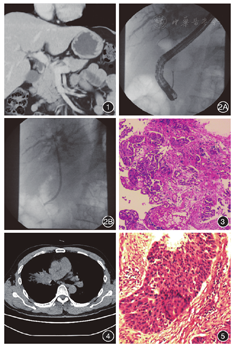

患者男,55岁,因"皮肤及巩膜黄染10余天"于2019年12月12日入院。患者皮肤和巩膜发黄,伴皮肤发痒、尿色深。患者2019年5月因右肺肿瘤行根治术,术后辅助化疗(紫杉醇240 mg d1+顺铂40 mg d1~2,20 mg d3, 4周期)。入院体检:体温36.1 ℃,脉搏89次/min,呼吸频率20次/min,血压102/72 mmHg(1 mmHg=0.133 kPa)。皮肤黏膜黄染,巩膜黄染。入院辅助检查如下,肝功能:总胆红素149.4 μmol/L,直接胆红素107.2 μmol/L,间接胆红素42.2 μmol/L,天冬氨酸氨基转移酶68.2 U/L,丙氨酸氨基转移酶158.3 U/L,谷氨酰转肽酶801.4 U/L,碱性磷酸酶483.1 U/L;肿瘤标志物:CA19-9 1.10 U/mL,甲胎蛋白2.54 ng/mL,癌胚抗原2.22 ng/mL,CA72-4 5.34 U/mL,CYFRA21-1 3.89 ng/mL。MRCP显示胆总管中段梗阻,肝内外胆管上段扩张,胆囊炎,肿瘤占位可能(图1)。内镜逆行胆管造影(endoscopic retrograde cholangiography,ERC)显示上段胆管扩张,中、下段胆管狭窄,狭窄长约4 cm。随后行内镜下乳头括约肌切开术(endoscopic sphincterotomy,EST)+胆管活检+胆管刷检,并行胆管扩张术及胆管塑料支架置入术(图2)。术后患者黄疸逐渐消退。胆管活检病理提示高度疑癌(图3),免疫组织化学显示CK7 (+), NapsinA (-), TIF-1 (-), CK5/6 (+), P63 (+), P40(+), Syn (-),CgA (-), CD56 (-), Ki-67 (约70%+), CK19 (+)。

患者7个月前被诊断为右肺鳞癌。PET-CT显示右肺上叶开口梗阻,局部软组织肿块影,放射性摄取异常增高,远端散在斑片状模糊影,有淋巴结转移的可能(图4)。因此,行肺癌根治性切除,术后病理示右上肺鳞癌,肿物大小4 cm×3 cm×2.8 cm(图5)。肿瘤浸润整个支气管壁,可见神经侵犯及肿瘤在静脉内堵塞,支气管切面未见癌变。第11组淋巴结转移至肺门和淋巴结(5/5,1/2)。7组淋巴结未见转移(0/4)。免疫组化结果显示CK7 (-), NapsinA (-), TIF-1 (-), CK5/6 (+), P63 (+), P40(+), Syn (-),CgA (-), CD56 (-), Ki-67 (约70%+),符合低分化鳞癌表现。胆管活检标本的免疫组化与原发性肺癌标本基本一致,由此认为是肺癌的胆管转移。